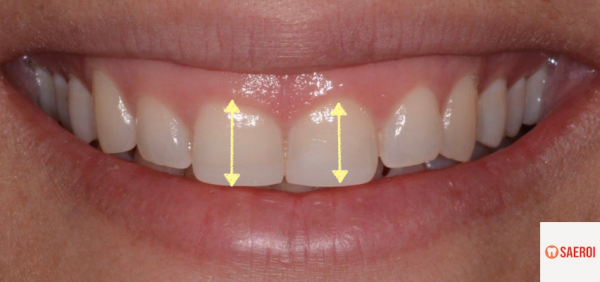

(3) 치관 길이가 짧은 경우

우리가 보는 치아의 모습은

치아 전체 형태 중에 '치관'이라고 하는

치아의 머리 부분입니다.

즉, 치아의 뿌리 부분은 잇몸 조직이 덮여있으며

잇몸이 과다하게 증식하여 치아를 많이 덮게 되면

치아의 머리 부분인 치관이

적게 노출되게 됩니다.

치아는 원래 세로가 가로보다 더 긴 모습을 보여야 하는데

짧은 치관은 가로가 더 긴 사각형 형태를 나타내며

웃을 때 잇몸이 더 많이 보이게 만드는 효과를 보입니다.